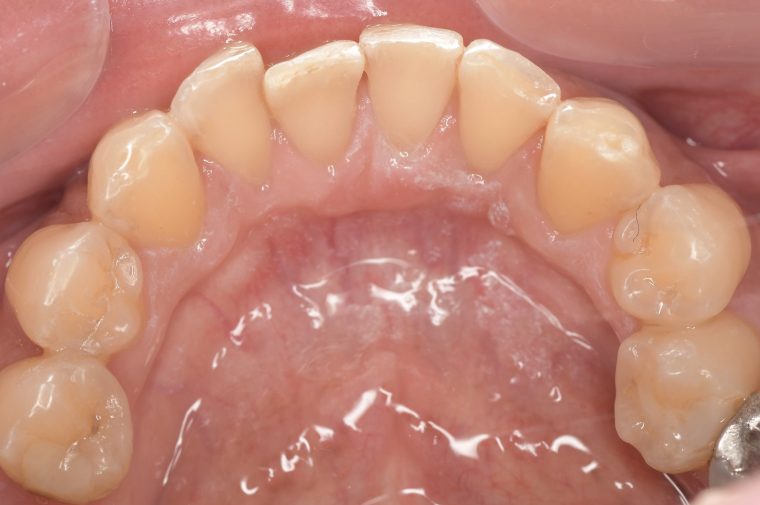

クリーニングの症例

現在の治療費と異なる場合がございます。最新の治療費は料金表をご確認ください。CASE 1

Before

After

基本情報

| 主訴 | 見た目をきれいにしたい |

| 治療期間 | 6ヶ月 |

| 治療費 | ジルコニアボンド(セラミックの被せもの)¥165,000×7(税込み) オフィスホワイトニング4回 ¥4,400×4(税込み) ホームホワイトニング¥11,000 |

| リスク・副作用 | かみ合わせがとても強い方の場合、稀に割れてしまうことがあります。 |

| 先生からの提案 | 上の前歯6本と右下の2番目の歯はセラミックの被せもので治療。 残りの下の前歯5本はプラスチックの材料で虫歯を治療し、 ホワイトニングをおこないました。白くなったご自身の歯の色に合わせてセラミックの 被せものを作成しています。 模型上で完成後をシュミレーションし、上の歯茎の位置をきれいに見えるように 揃えています。(外科処置はしていません) |